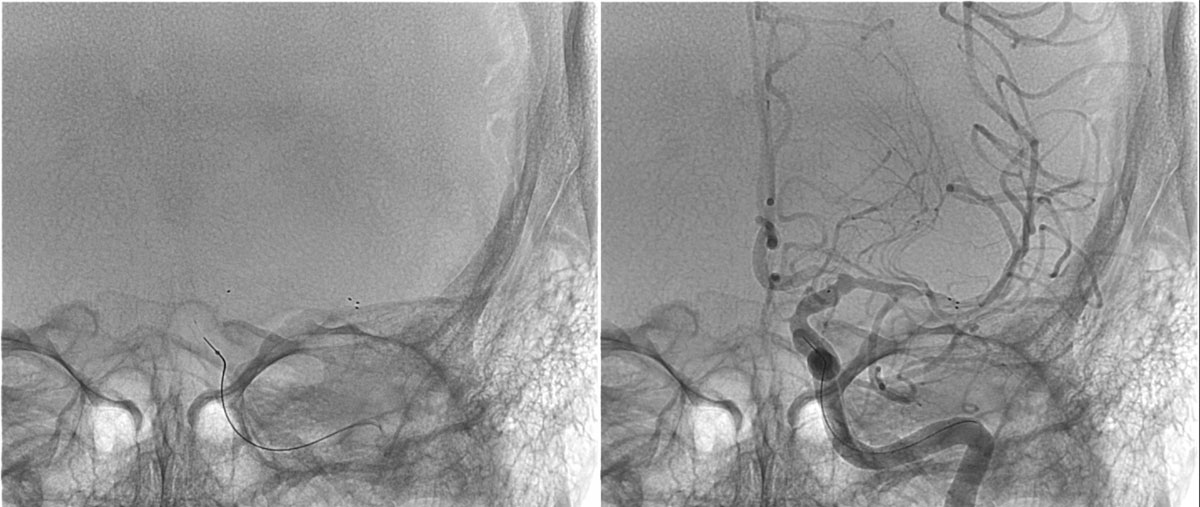

DSA

L - VERT

L - ICA